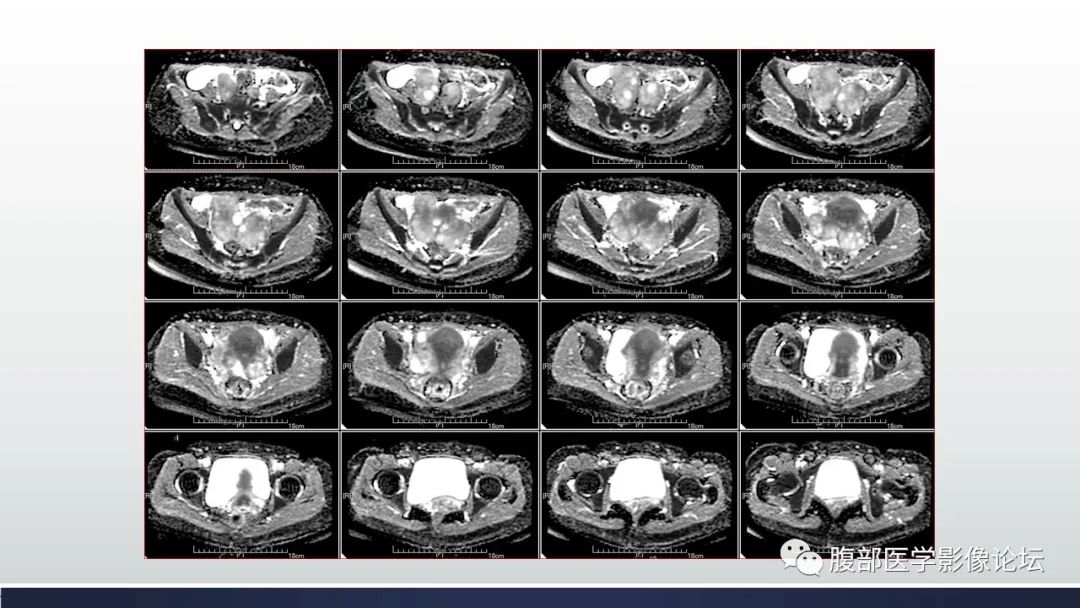

【病例】子宫内膜透明细胞癌1例MR-1

【病例】子宫内膜透明细胞癌1例MR-2

【病例】子宫内膜透明细胞癌1例MR-3

【病例】子宫内膜透明细胞癌1例MR-4